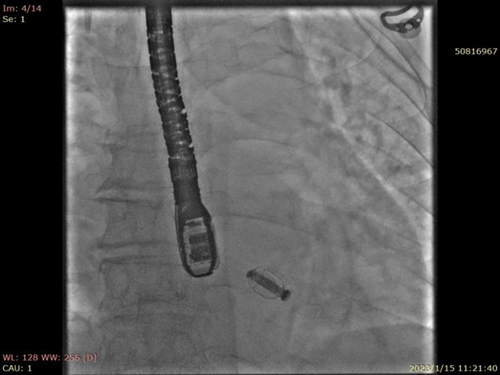

2023-1-15全麻下安排行二尖瓣钳夹术,术中首次使用国产端佑Neonova二尖瓣夹合系统,成功捕获瓣叶,予以夹闭后反流达到极微量反流。